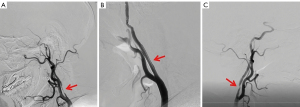

Stenting procedure and medication after stenting

Stenting was performed by a well-trained neurointerventional specialists team with more than 10 years of experience in .the second hospital of Hebei Medical University. Four professional neurointerventionists completed all the stents in this study, and their specialty was neurointerventional therapy. All enrolled patients were managed with dual antiplatelet therapy (aspirin 100 mg and clopidogrel 75 mg daily) for at least 3 days before stenting. A bolus of intravenous heparin (50 IU/kg of body weight, 3,000–5,000 IU) was injected after the guide catheter. The intervention therapy was performed via the femoral artery route, a guiding catheter was placed into the CCA, and a suitable size of stent was implanted. In our study, the closed stents included Wallstent and Enterprise, and the opened stents included EV3 and Acculink. The open stent was preferred for vessel tortuosity and angulation, and the closed stent was preferred for significant ulcerative plaques or unstable soft plaques. In the absence of these conditions, the surgeon determined the stent type. After successful stent implantation, the residual stenosis rate was evaluated with cerebral angiography. Angiography of the C1 segment of the ICA before and after stenting is shown in Figure 2.